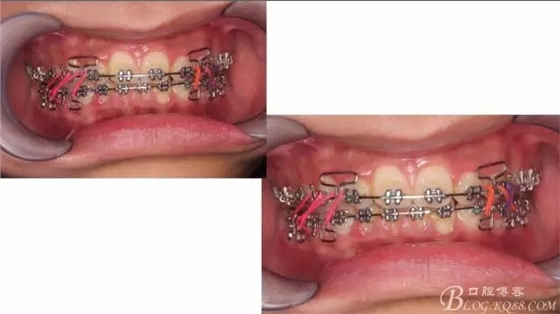

佩戴三個(gè)月的FR2, 效果奇佳!前牙基本達(dá)到淺覆蓋,淺覆合!接下來進(jìn)入二期直絲弓固定正畸,排齊階段!

接下來盡管配合些雙側(cè)后牙對(duì)角牽引,咬合關(guān)系依,不盡人意。

下頜配合多曲方絲,三角牽引,調(diào)整咬合。

中線不齊,咋辦?繼續(xù)哄哄患者配合,2牽+斜牽。

努力沒有白費(fèi),中線基本對(duì)齊!